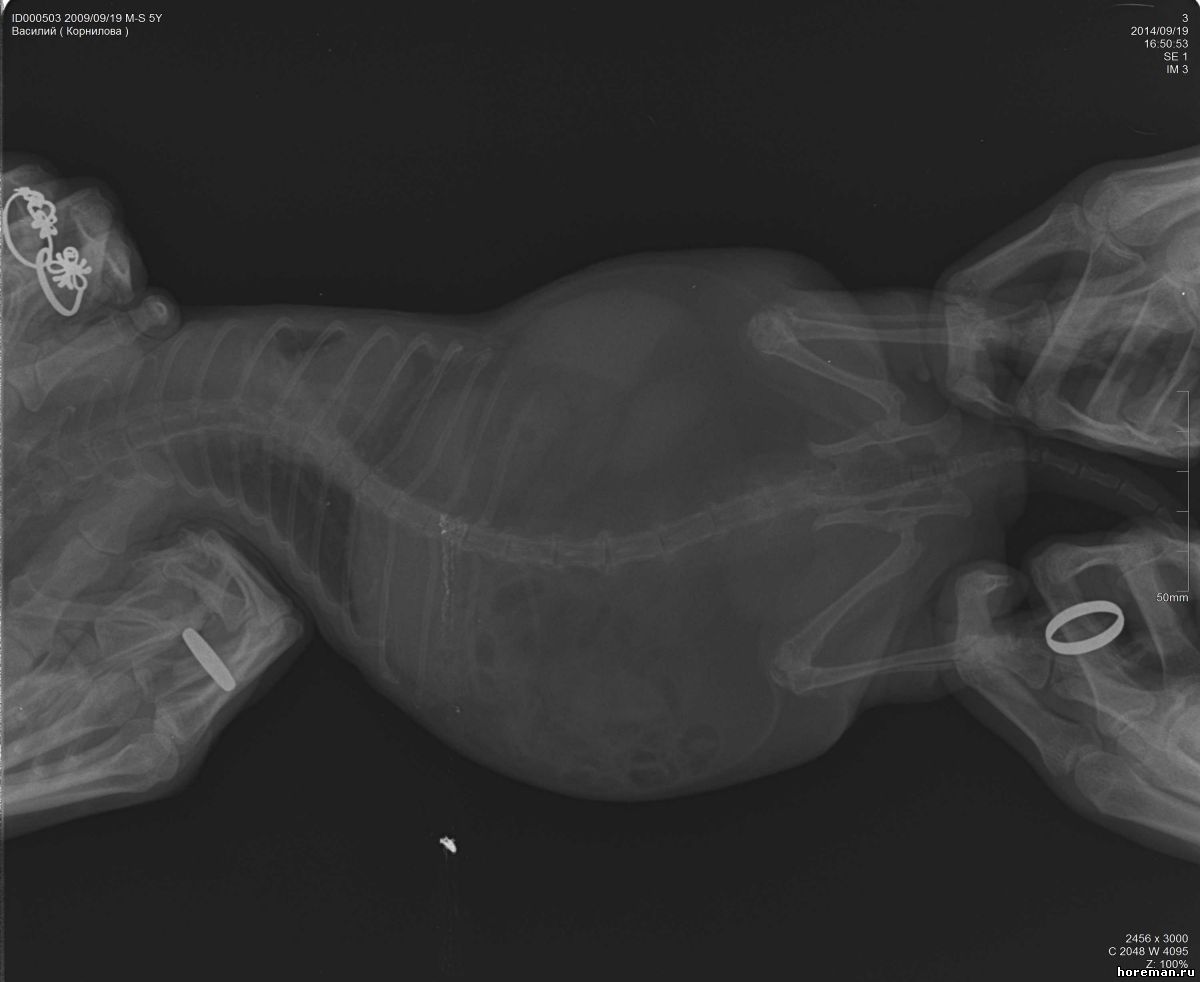

Добрый день! Нужно Ваше мнение по снимкам позвоночника моего хорька. 5 лет, кастрирован. Проблема с позвоночником, ползает на задних лапах, болевых ощущений нет, так же энергичен, игрив. Анализы все хорошие. Снимки не очень хорошего качества, завтра переделаем, но все же....

Подскажите.....Мнения нашего вета это защимление нервов в грудном отделе и что то там с позвонком выше поясницы, говорит нужна операция нейрохирургическая... :'(

Прикрепленный файл: 1991322.jpg (51.9 Kb) · 0357150.jpg (62.6 Kb) · 7876473.jpg (55.9 Kb)